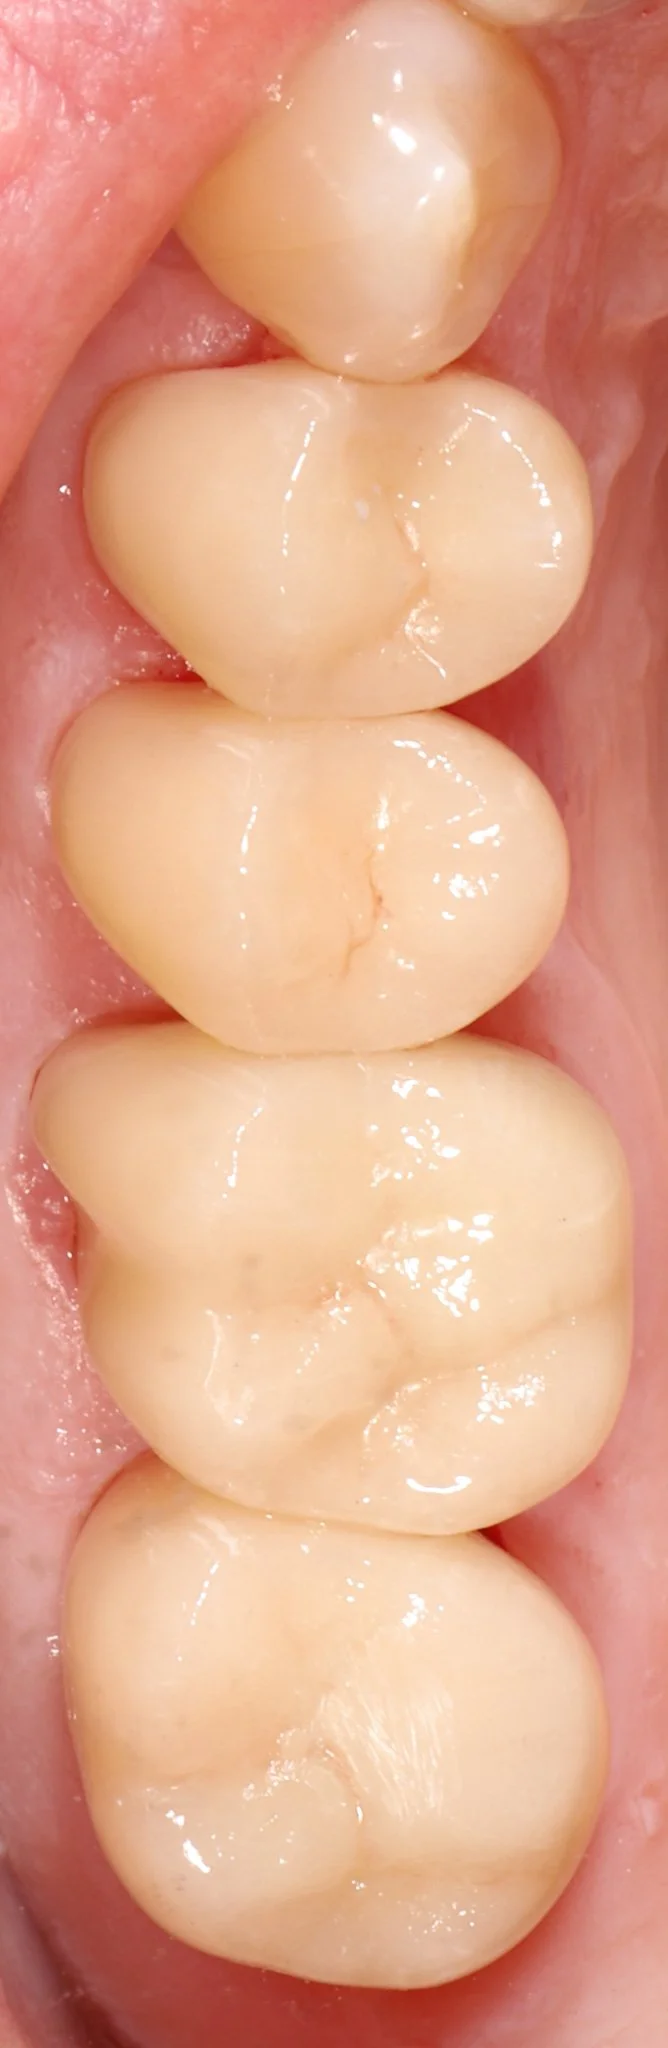

Close-up of four back molars in a person's mouth, showing clean, healthy, light-colored teeth.

After: Bonded porcelain to seal and protect teeth